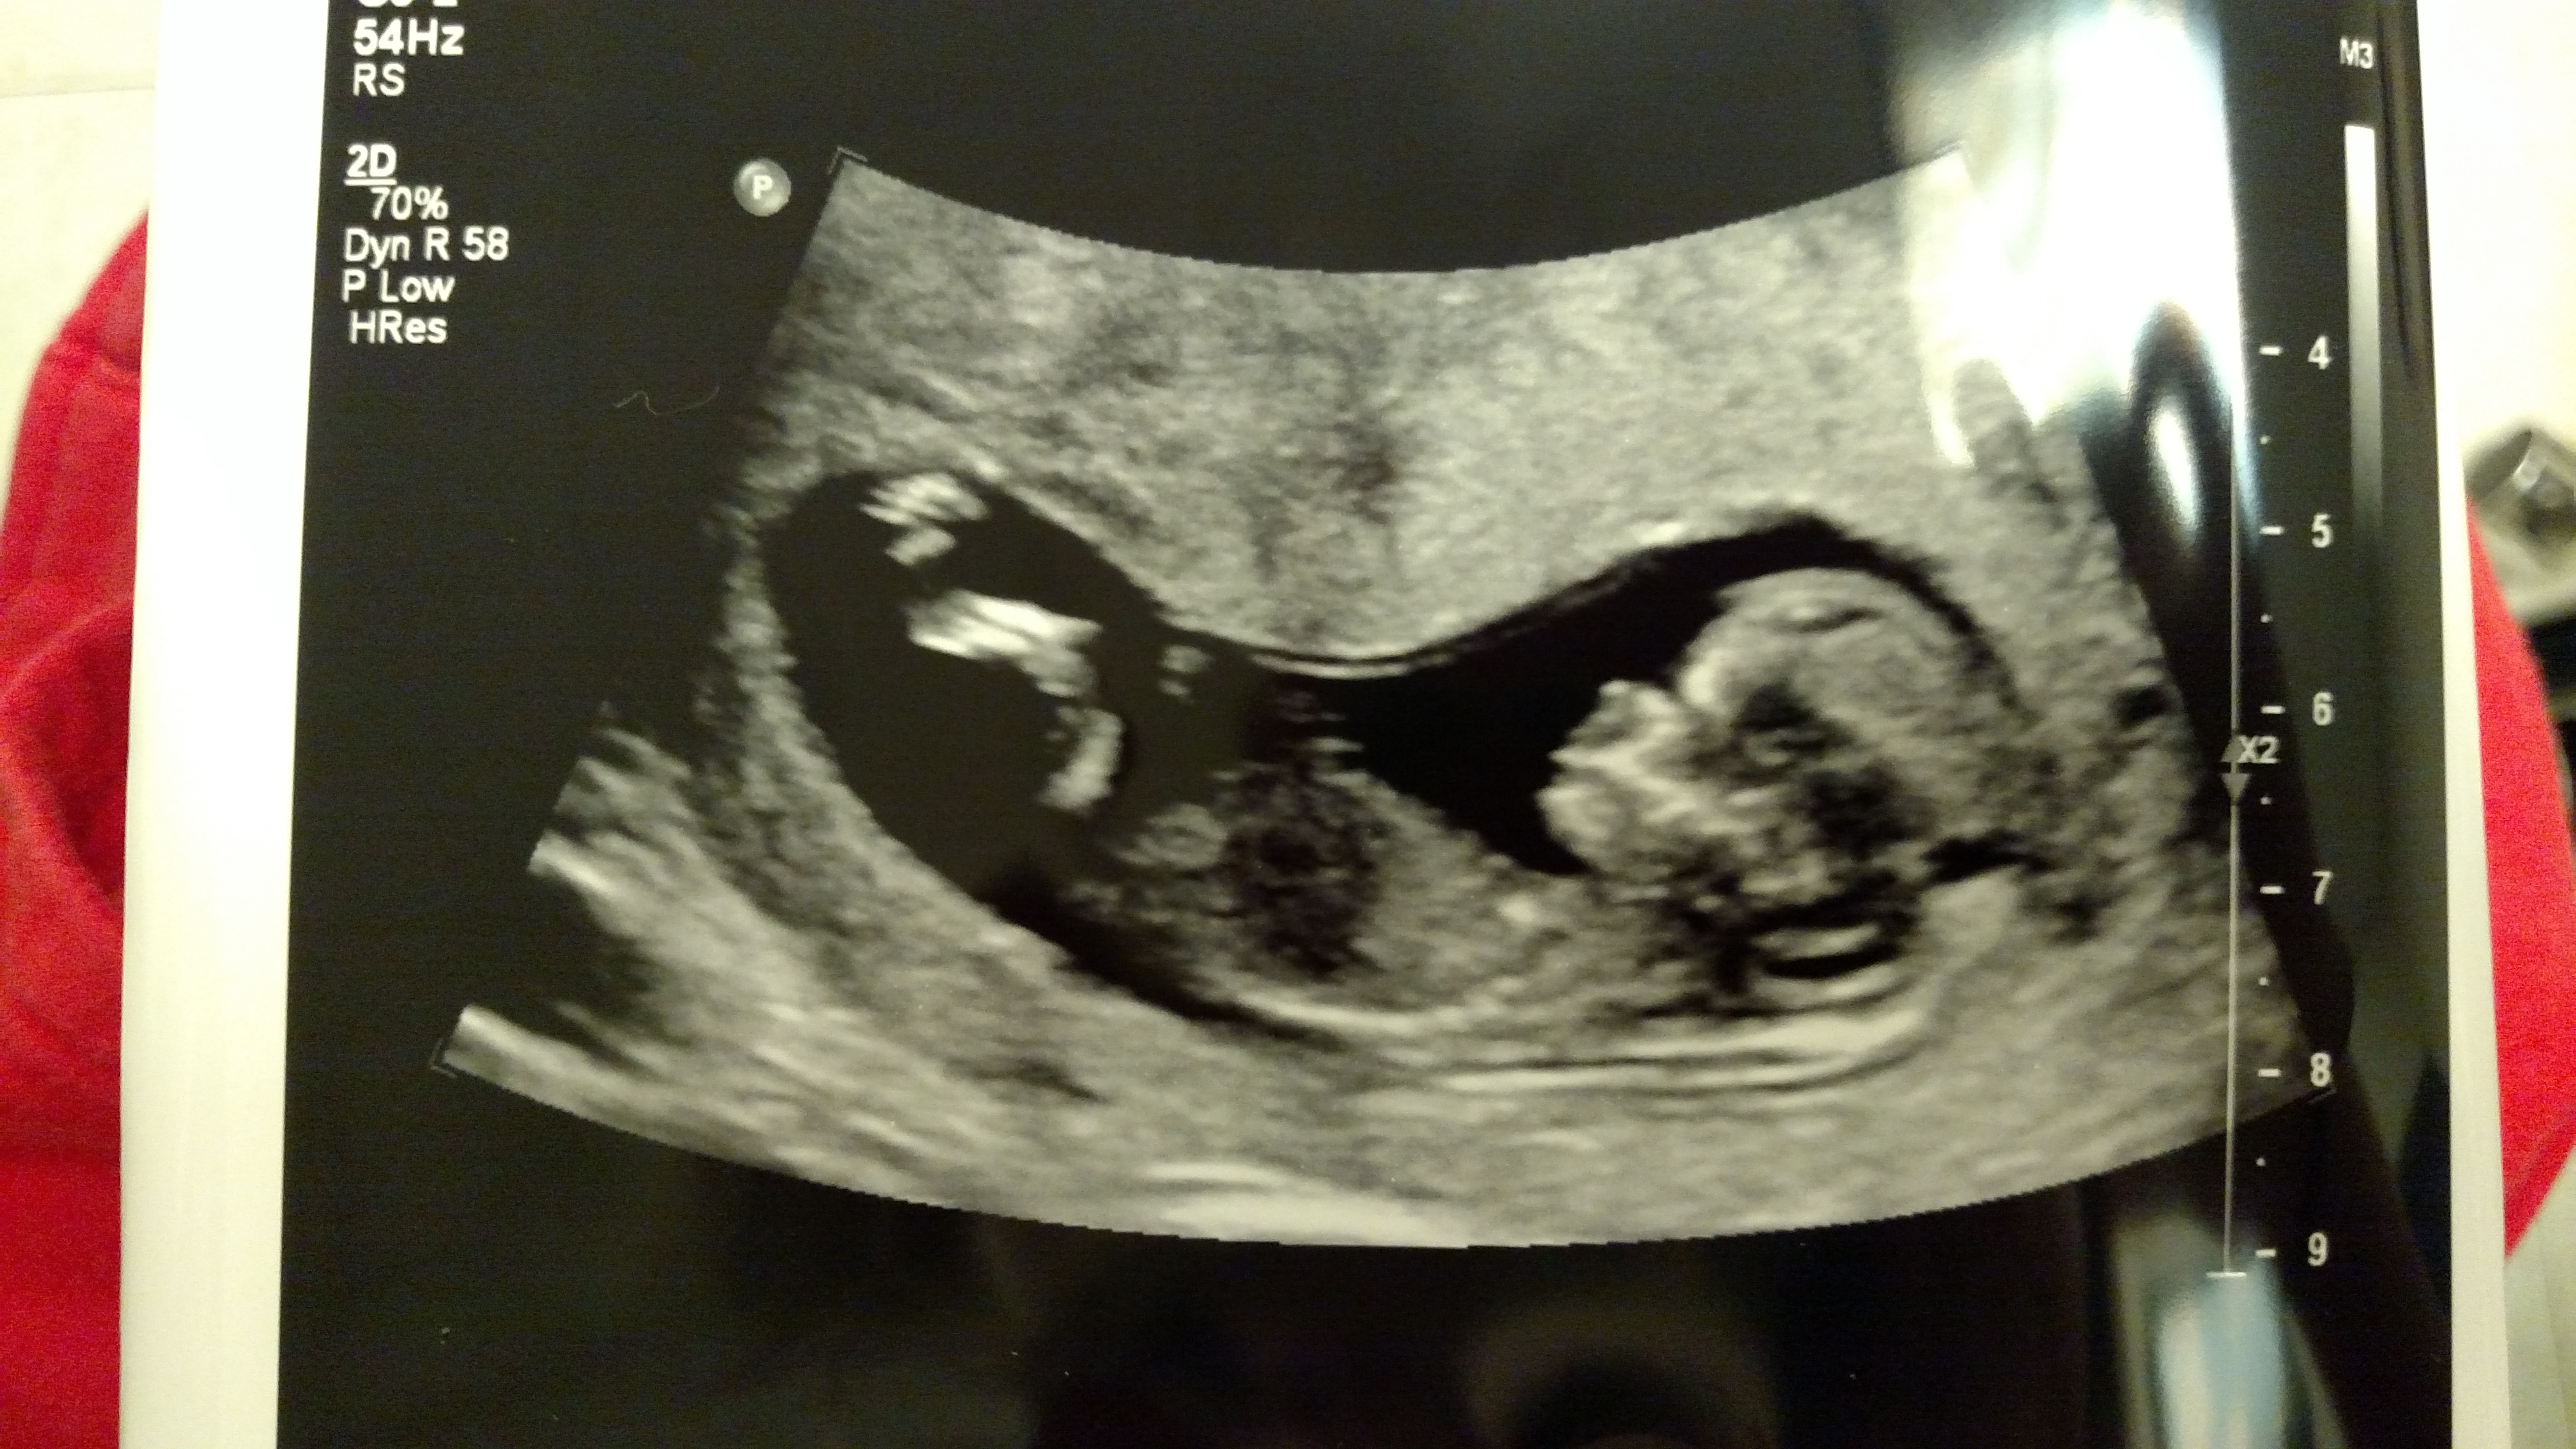

No nub here. But I will give just a fun guess for skull shape. ... guessing boy!

No nub on 2d but leaning boy aswell incase the maybe nub? on 4d seems quite angled up. What gestation was this? :)

It is 12 weeks 3 days